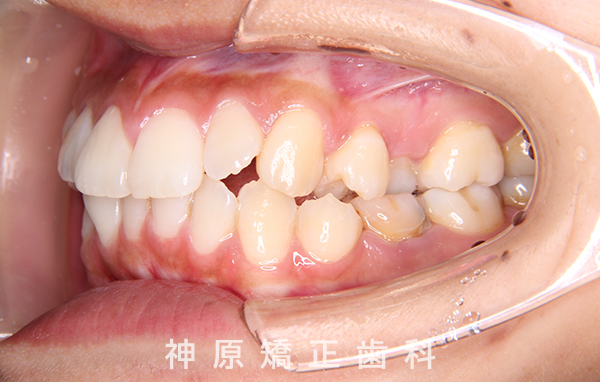

初診時

マルチブラケット装着1年後